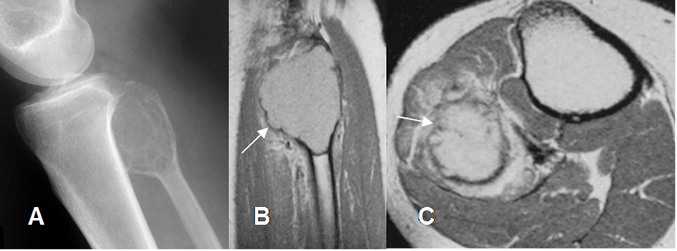

Fig 120. Tumor de células gigantes.

Rx AP. Imagen excéntrica, lítica y parcialmente definida, en la metáfisis tibial, por tumor de células gigantes.

Fig 121. Tumor de células gigantes.

TAC reconstrucción coronal. Imagen expansiva y lítica, en el alerón del sacro, sin ruptura de la cortical, por tumor de células gigantes.

Fig 122. Tumor de células gigantes.

A: Rx lateral, B: RM coronal en T1 y C: RM sagital en T2. Lesión metafisiaria hipointensa en T1 e hiperintensa en T2, que rompe la cortical y forma una seudocápsula hipointensa en ambas secuencias.

Fig 123. Tumor de células gigantes.

A: Rx lateral. Lesión expansiva y sin ruptura de la cortical, en la cabeza del peroné.

B: RM sagital y C: RM axial en T1 con contraste. Formación de seudocápsula y gran realce del contraste.